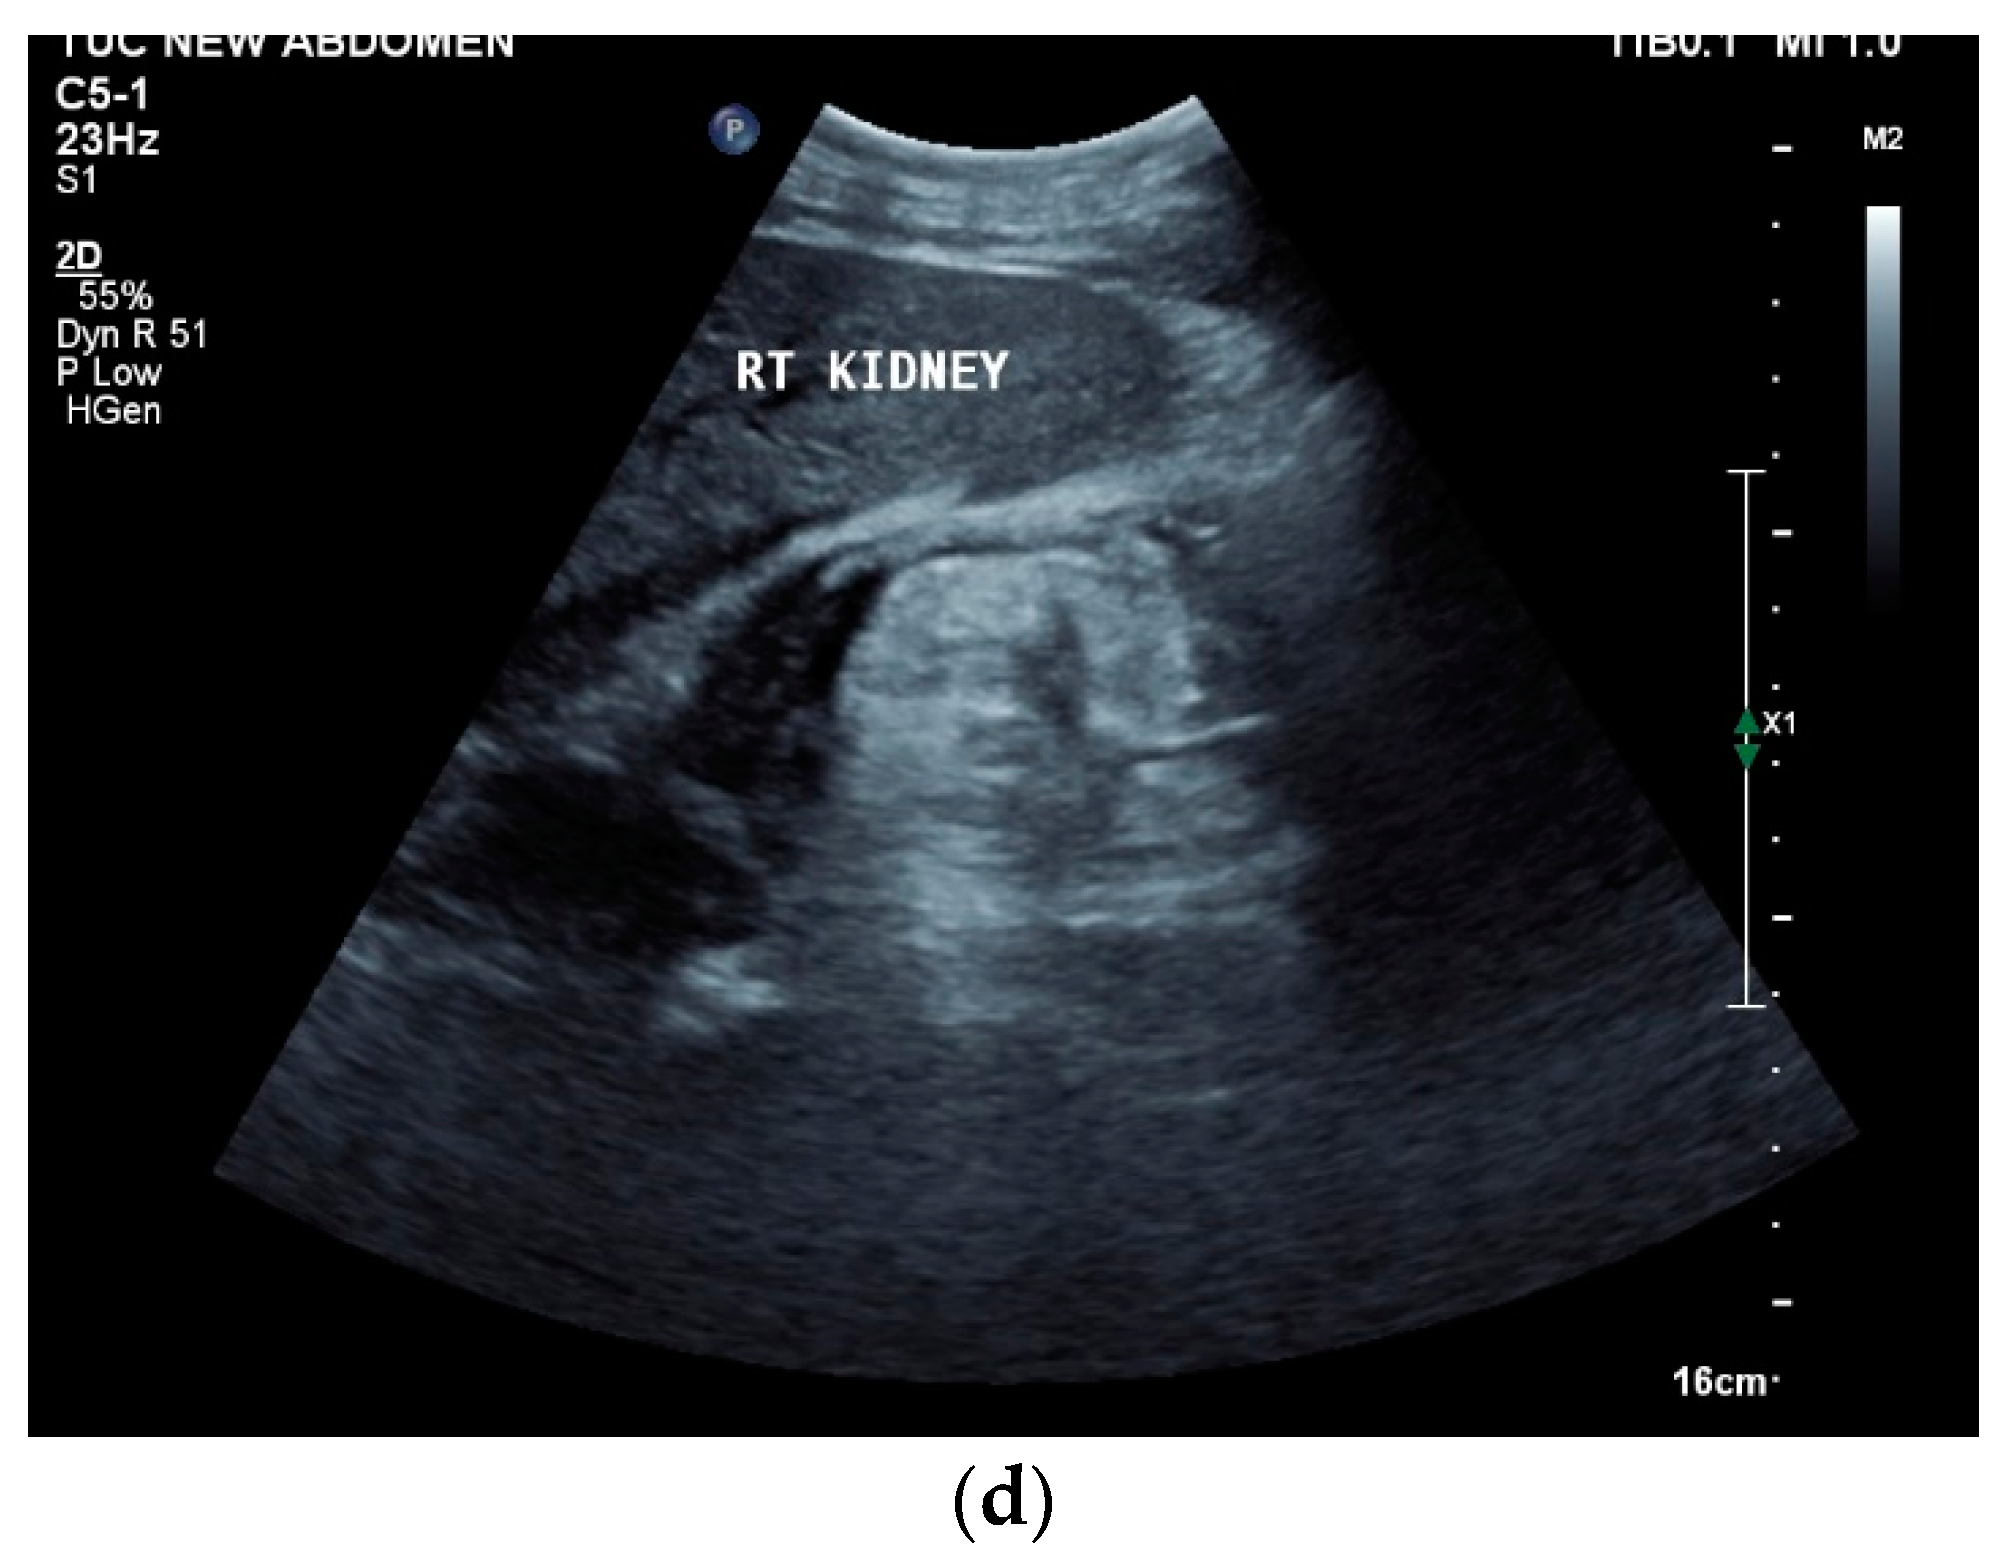

When using multiparametric ultrasound, the majority of superficial lymph nodes showed marginal blood flow during Color Doppler Imaging. When using CEUS, marginal/annular enhancement, separation enhancement, and heterogeneous enhancement was observed [42]. When using elastography, either type 1—Red or yellow-green or type 2—Blue < 45% have been described. However, elastography type 3 was also a typical finding in another endoscopic ultrasound (EUS) study [43]. It is conceivable that the elasticity depends on the stage of the disease, the presence of necrosis, or the development of fibrosis. Histologically evaluable material can be obtained from superficial lymph nodes or abdominal lymph nodes, accessible via percutaneous ultrasound-guided biopsy. The aim is to detect granulomatous inflammation, epithelioid cell granulomas, Langerhans cells, caseous necrosis, and the presence of Mycobacterium tuberculosis. Enlarged cervical lymph nodes are easily accessible for ultrasound-guided biopsy. The sensitivity and specificity of histologic diagnosis were 70.1% and 100%, respectively. The sensitivity and specificity of Xpert for cervical tuberculous lymphadenitis diagnoses were 82.5% and 97.5%, respectively [44]. The acquisition of histologically evaluable material can be improved by differentiating the lymph node structure in CEUS. Solid vital tissue can be differentiated from areas of necrosis. The CEUS-guided biopsy of lymph node tuberculosis has a high sampling success rate of 94.5% [44].

Mediastinal lymph nodes can be biopsied using EUS- or EBUS-guided FNA or FNB. Via paraoesophageal, paragastric, and paraduodenal access, histological specimens can be obtained from further lymph nodes using EUS-guided sampling [41,43,45,46,47,48,49,50] [Figure 2a–m]. The most important differential diagnoses are metastases of malignant tumors, non-Hodgkin’s and Hodgkin’s disease and other infections.

Figure 2.

A case of extrapulmonary tuberculosis: 33 y/o male from a country at high risk of tuberculosis. Thoracic pain and fever led to a suspicion of pericarditis. There was no pericardial effusion. There were no pulmonary infiltrations or pleural effusions in the chest CT, but there were enlarged mediastinal lymph nodes. Ultrasound and CT also showed subdiaphragmal enlarged lymph nodes and small nodular splenic changes. The diagnosis was confirmed using the transgastric EUS-guided biopsy (19 G Olympus) of the lymph nodes in the hepatic hilum. Enlarged lymph nodes in the hepatic hilum (a); adjacent to the pancreatic head (b); transabdominal ultrasound (TUS) using a linear transducer of 9 MHz. The hypoechoic central parts are conspicuous (a,b). Rounded lymph nodes are observed as being peripancreatic (c) and as being in close proximity to the gallbladder wall (d). The lymph nodes are visualized between the markers. In the EUS, paragastric lymph nodes are enlarged, rounded, very hypoechoic, with hypoechoic central parts, and forming conglomerates. A central vascular hilum cannot be delineated in the CDI (e). The hypoechoic central parts are softer during elastography (f). EUS also shows enlarged hypoechoic lymph nodes in the hepatic hilus, with hypoechoic central parts that lack a central vascular hilum (g). Elastographically, the lymph nodes are indifferent (h). The diagnosis is confirmed using EUS-guided biopsy (i) with evidence of granulomatous inflammation, caseous necrosis, detection of acid-fast rods, and Mycobacterium tuberculosis in the PCR. In the spleen, single hypoechoic lesions < 5 mm are visible during transabdominal ultrasound using a linear transducer of 9 MHz. Otherwise, fine-grained hypoechoic lesions can only be guessed at (j). With magnification using a 9 MHz transducer, multiple hypoechoic lesions < 3 mm can be delineated (k). These do not reveal any vessels in the Power Doppler (l). EUS confirms multiple hypoechoic splenic lesions, in line with splenic tuberculosis (m).